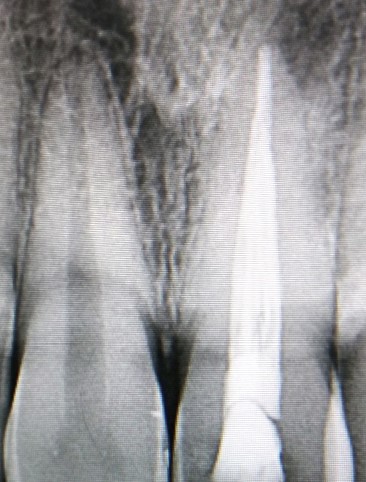

PRE - OP RADIOGRAPGH WORKING LENGTH MASTER CONE

COLD LATERAL COMPACTION OBTURATION